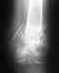

Re: Открытый перелом обеих костей голени 27 лет, Таиланд, необходима консультация

послал Alexander Chelnokov 19 Май 2012, 12:10

Операцию, конечно, лучше сделать. Вопрос - когда лучше. Тут определенного одного ответа нет. Можно оперировать было как закрытый перелом. Можно и подождать заживления раны. Можно и оперировать как открытый перелом, в два этапа - санчала аппарат, а после заживления раны - внутренняя фиксация.